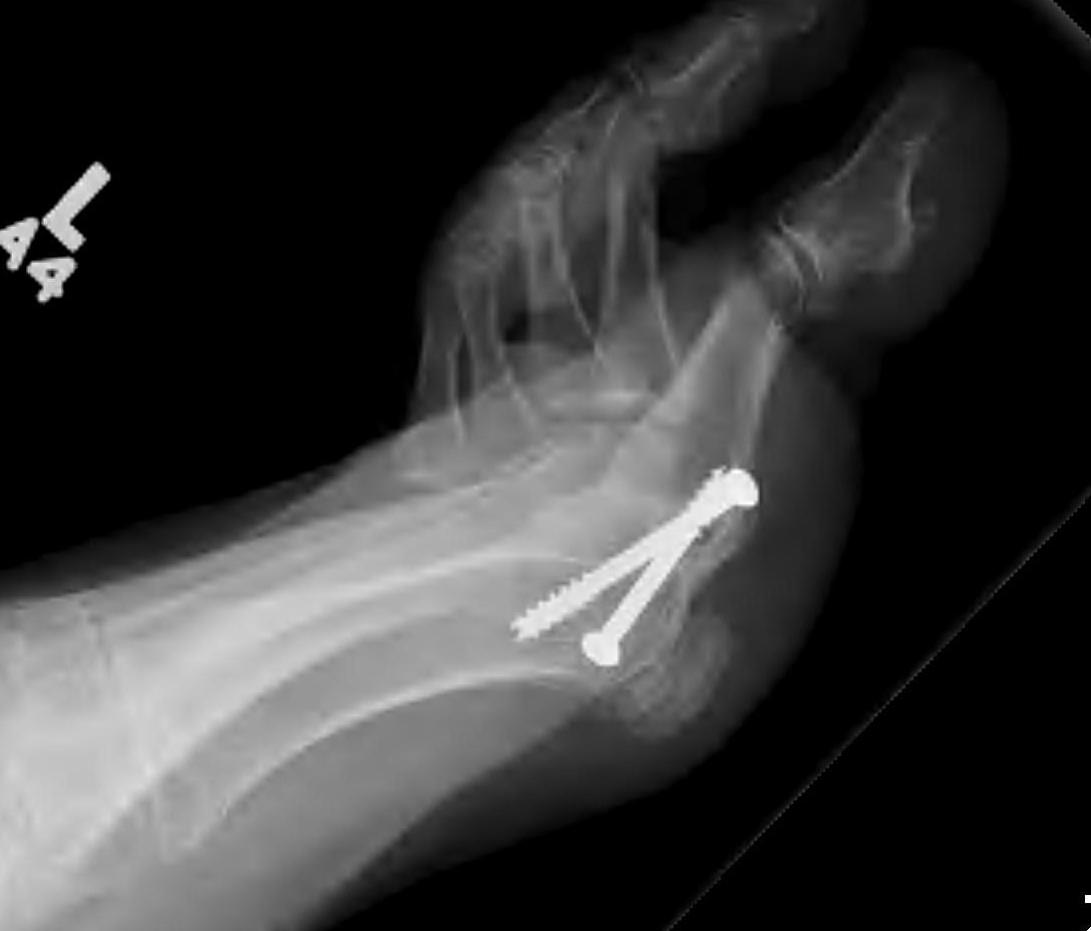

Arthrodesis

Indication

- advanced OA

- young, active patient

Screw fixation

Plate fixation

Screw + plate fixation

Fixation

- screws / plate / screws + plate

Results

- 4 year follow up of 60 1st MTPJ fusion

- screw + plate

- 93% fusion

- remainder painless pseudoarthrosis

- 72% very satisfied, 18% satisfied